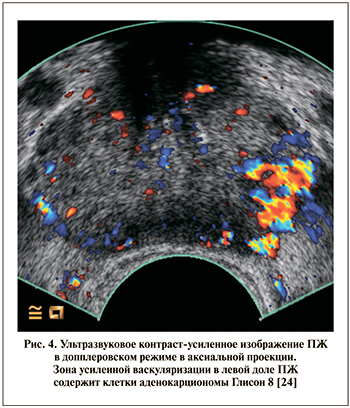

Контраст-усиленное ТРУЗИ (contrast-enhanced-TRUS, CE-TRUS)

«Усиление» изображения во время серошкального УЗИ возможно с помощью специальных контрастных веществ, которые представляют собой стабилизаторы пузырьков газа (воздуха), вводимые внутривенно. Пузырьки газа позволяют визуализировать обширное микрососудистое русло, окружающее опухолевый очаг. Как правило, контраст-усиленное УЗИ выполняется в допплеровском режиме. Такое усиление изображения позволяет делать прицельные заборы тканей из областей, наиболее вероятно содержащих злокачественные клетки (рис. 4).